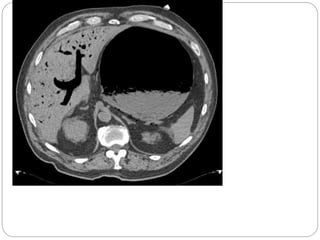

Plain film changes-

 Chest x-ray-

o Left sided pleural effusion

o Splinting of left hemidiaphragm

o Basal atelactasis

 Abdominal film-